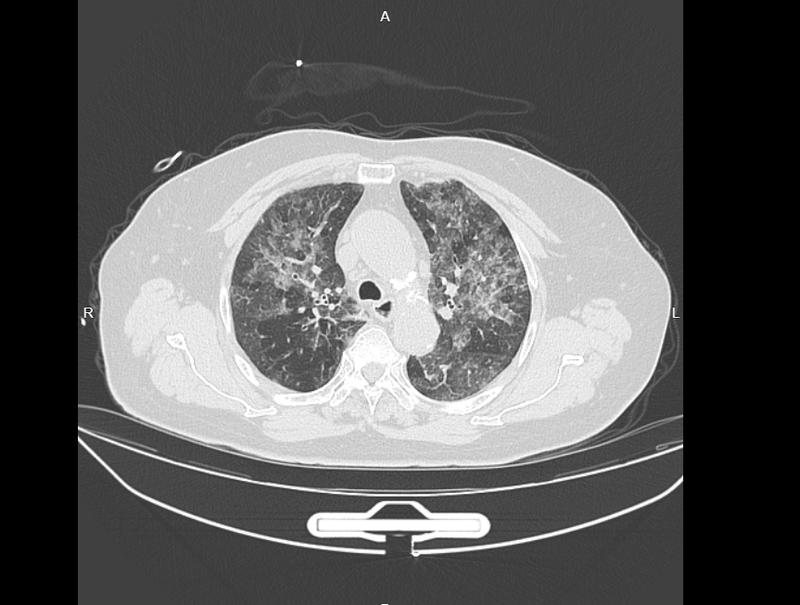

近年来,一些看似寻常的生活习惯却悄然成为健康隐患。71岁的张奶奶原本生活规律,身体素来硬朗,然而去年夏季,她突感咳嗽不止、痰多且伴有明显气促。起初以为是普通感冒,在本地医院接受抗感染治疗十余天,症状却毫无缓解迹象。无奈之下,她前往宁波大学附属第一医院呼吸与危重症学科求诊。接诊的丁群力主任医师通过胸部CT检查,发现肺部呈现大片弥漫性白影,俗称“白肺”,影像上密布细小白斑。肺功能评估仅为正常六成,稍有活动便气喘吁吁,严重影响日常生活质量。由于常规抗生素无效,且临床表现符合外源性过敏性肺泡炎特征,医生及时采用激素治疗,症状暂时得到控制,并指导患者回顾可能接触的刺激源。

数月后,张奶奶病情再度急剧恶化,咳喘程度加重,复查影像显示炎症范围扩大,各项指标明显异常。医生团队与家属共同分析发病前后生活细节,逐一排除常见诱因如家居装修粉尘、宠物亲密接触等,最终锁定一个特殊习惯:为子孙祈求福祉,她经常整日待在香火浓郁的场所。香火燃烧释放的细微颗粒在密闭空间内浓度较高,易被深吸入肺。这些颗粒刺激免疫系统,激活巨噬细胞等,引发连锁炎症反应,损伤肺泡和间质组织。丁群力医师强调,这种过度免疫应答如同“自伤”,长期持续可能导致肺纤维化等不可逆改变。患者听后深受触动,承诺今后避免类似暴露。经过持续规范干预,近期复诊显示肺部白影显著减少,肺功能接近正常八成,虽留有轻微痕迹,但恢复前景乐观,需要长期维护。

类似情况在临床中屡见不鲜。例如,80岁李大爷在乡村焚烧秸秆时吸入大量浓烟,迅速出现高热、胸闷和呼吸窘迫,甚至发展至缺氧状态。入院检查同样为双肺弥漫白影,因高龄及心脏基础疾病,进展迅猛。经激素及时干预,短期内症状明显改善,肺损伤基本消退。